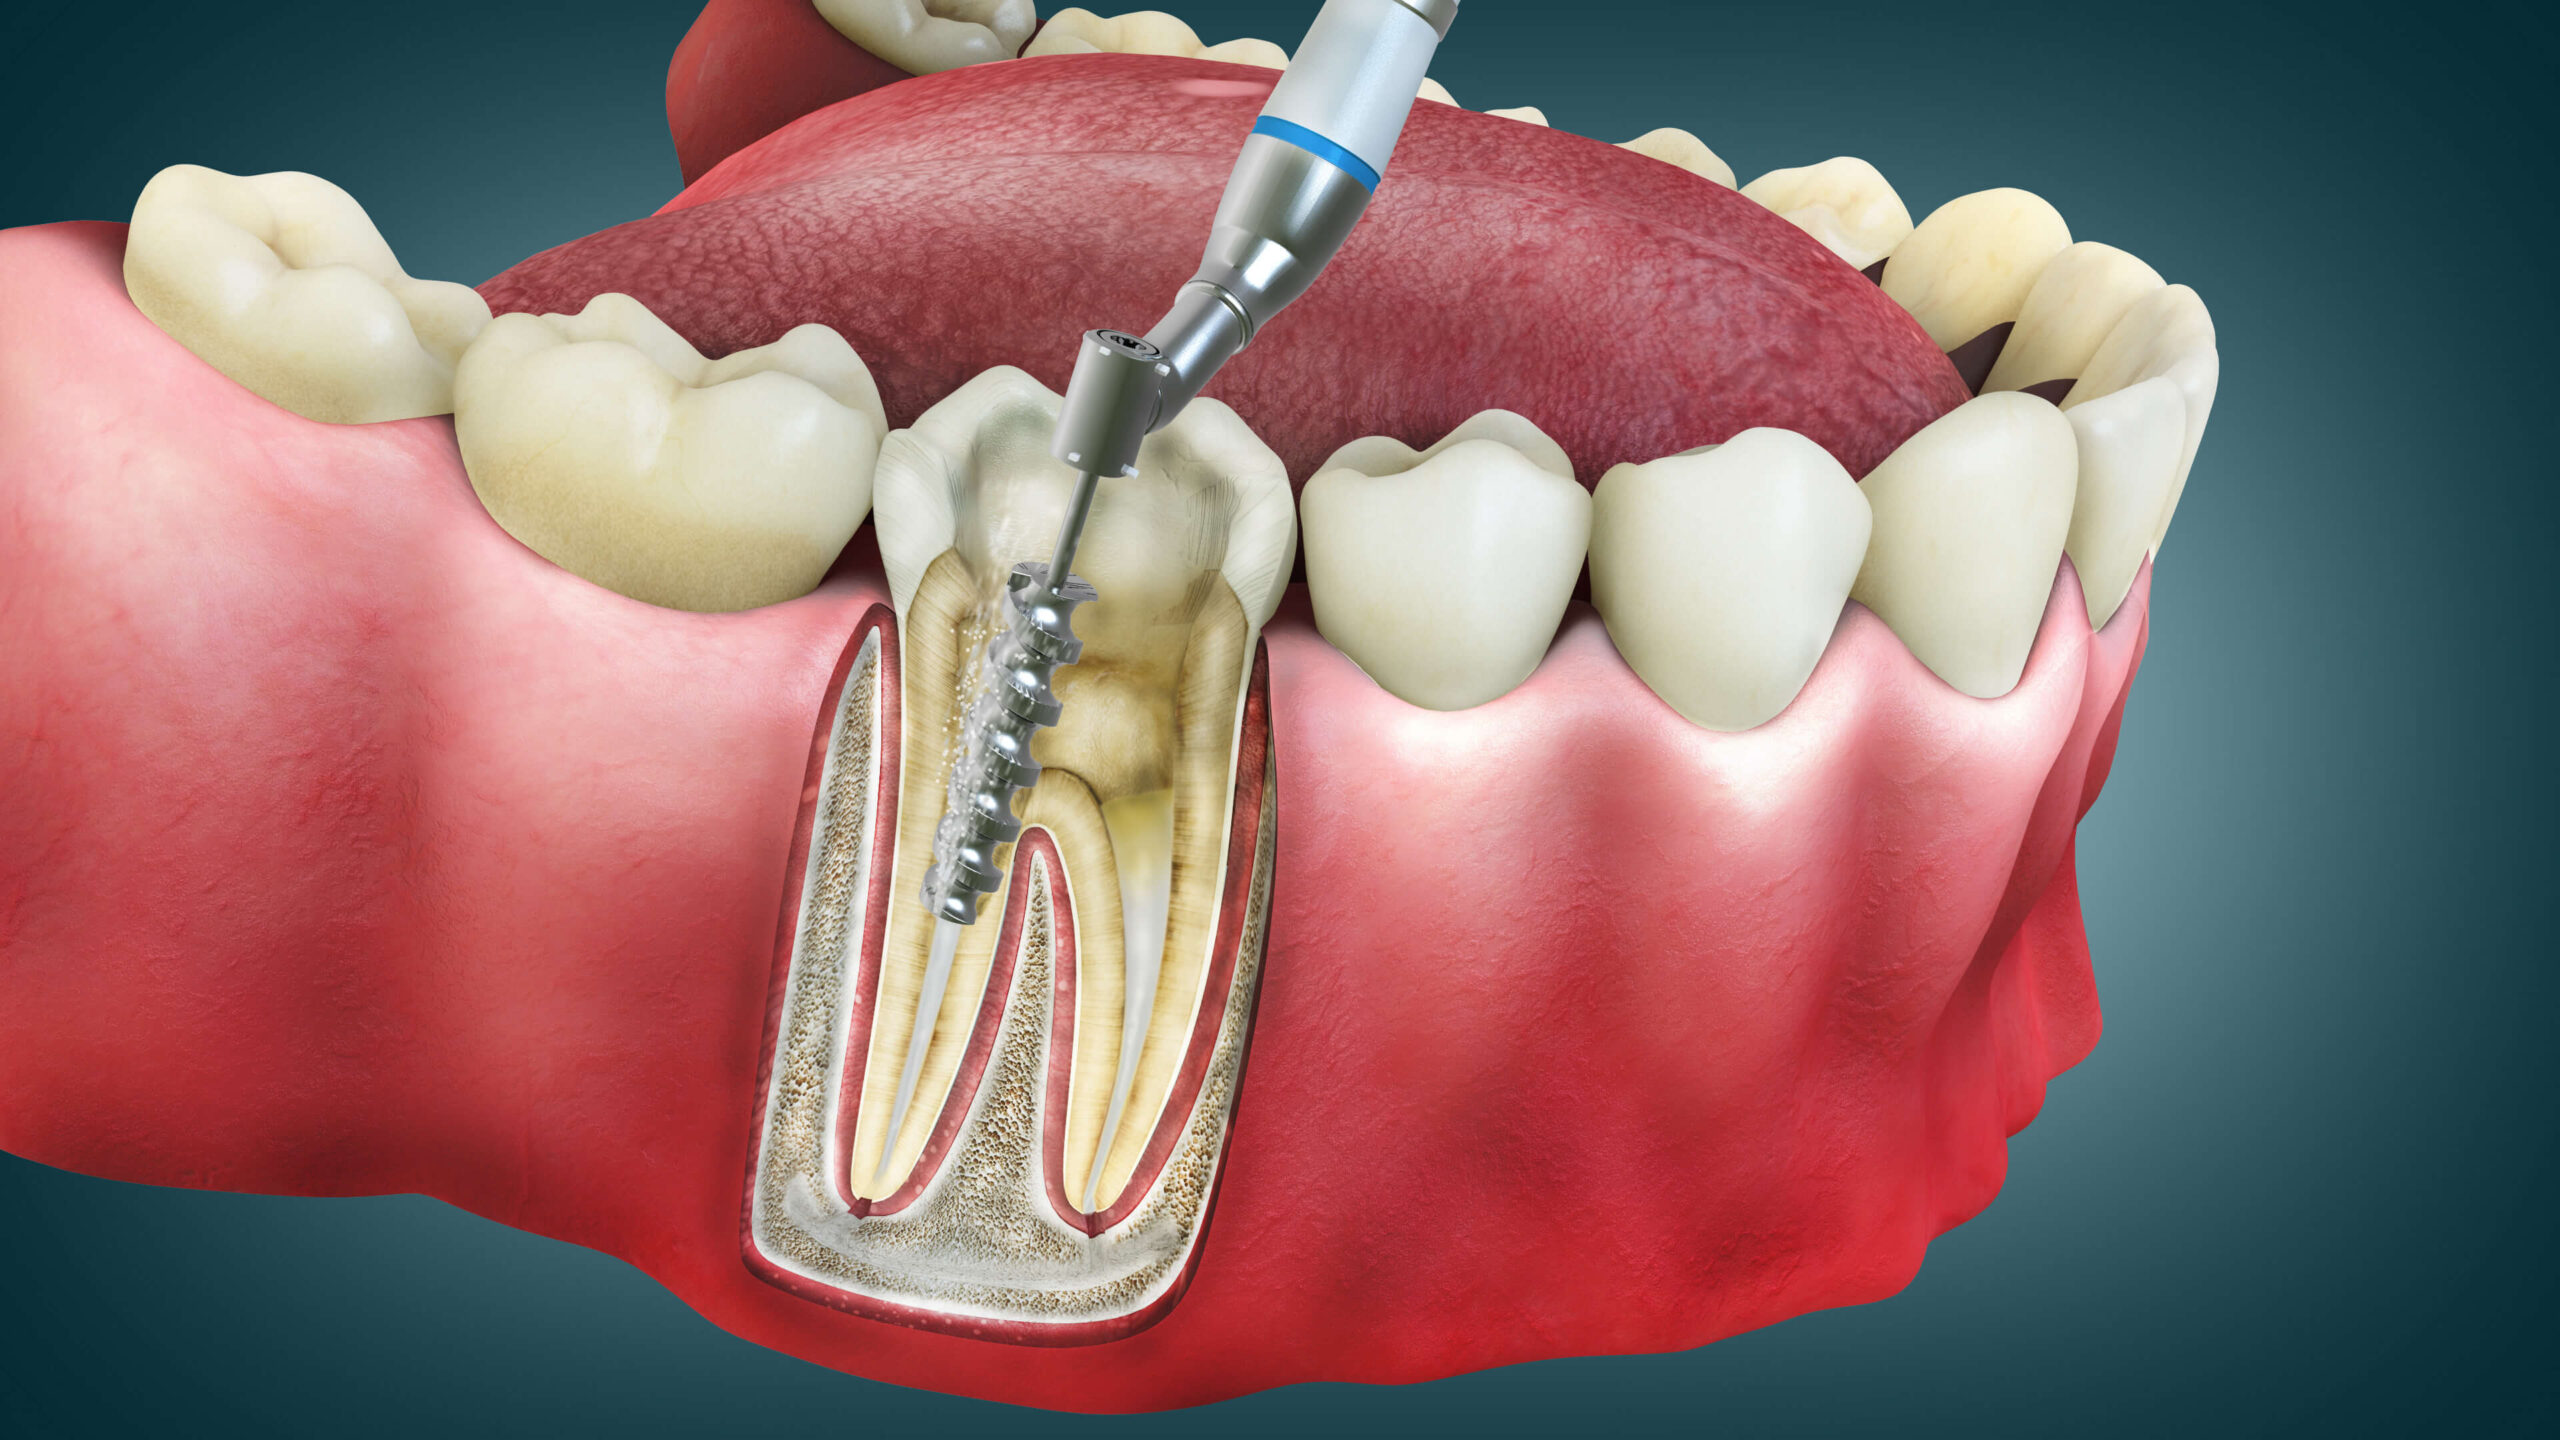

Root canal treatment, also known as endodontic therapy, is a dental procedure designed to save a severely damaged or infected tooth. When the innermost part of a tooth, called the pulp, becomes infected or inflamed due to deep decay, trauma, or repeated dental procedures, a root canal is necessary to remove the infected pulp and save the tooth from extraction. The procedure involves cleaning, disinfecting, and sealing the tooth to prevent further infection.

At Mackay Family Dental, we specialize in providing effective and comfortable root canal treatment. Our dental professionals will begin by examining your tooth and assessing the extent of the infection. The procedure is performed under local anesthesia to ensure your comfort. We will carefully remove the infected pulp, clean the root canals, and seal the tooth with a filling material. In some cases, a dental crown may be recommended to protect and strengthen the treated tooth.